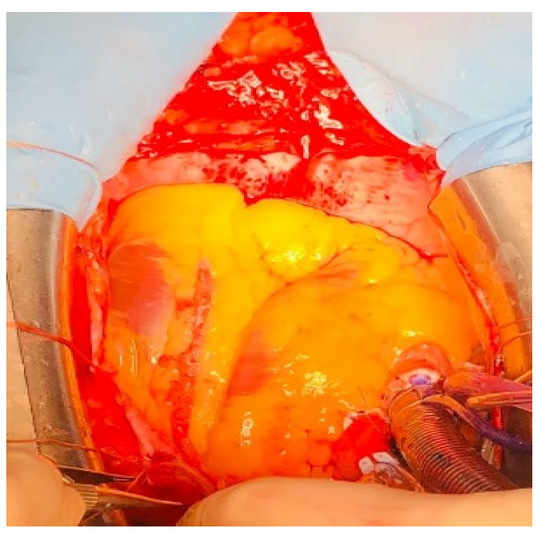

Our Technique